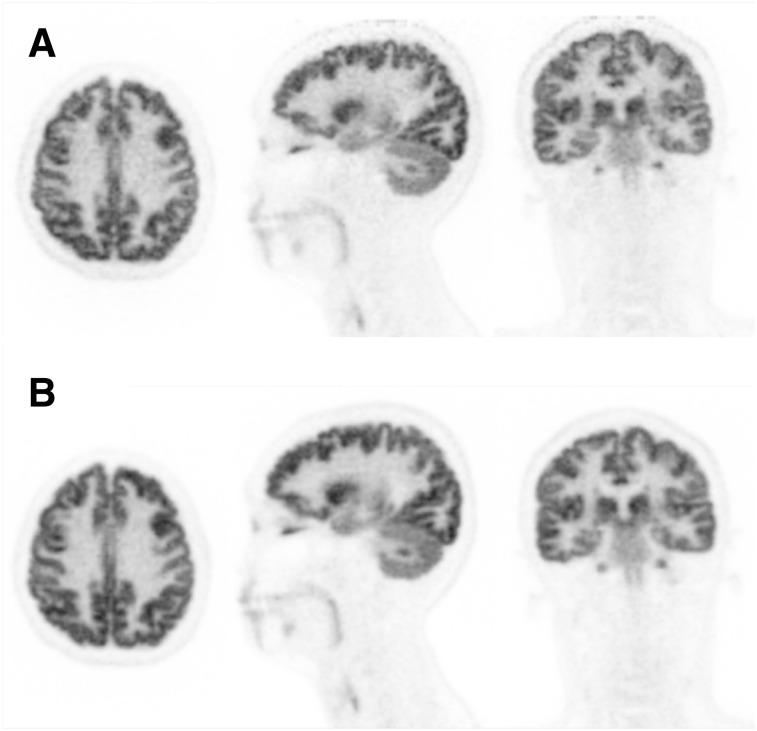

We report on the development of the PennPET Explorer whole-body imager. The PennPET Explorer is a multiring system designed with a long axial field of view. The imager is scalable and comprises multiple 22.9-cm-long ring segments, each with 18 detector modules based on a commercial digital silicon photomultiplier. A prototype 3-segment imager has been completed and tested with an active 64-cm axial field of view. The instrument design is described, and its physical performance measurements are presented. These include sensitivity of 55 kcps/MBq, spatial resolution of 4.0 mm, energy resolution of 12%, timing resolution of 256 ps, and a noise-equivalent count rate above 1,000 kcps beyond 30 kBq/mL. After an evaluation of lesion torso phantoms to characterize quantitative accuracy, human studies were performed on healthy volunteers. The physical performance measurements validated the system design and led to high-quality human studies.

我们报告了 PennPET Explorer 全身成像仪的开发情况。PennPET Explorer 是一款多环系统,设计具有长轴向视野。该成像仪具有可扩展性,由多个 22.9 厘米长的环段组成,每个环段都有 18 个基于商用数字硅光电倍增管的探测器模块。已经完成了一个具有主动 64 厘米轴向视野的 3 段式原型机,并进行了测试。本文描述了仪器的设计,并介绍了其物理性能测量结果。这些结果包括 55 kcps/MBq 的灵敏度、4.0 毫米的空间分辨率、12%的能量分辨率、256 ps 的时间分辨率以及在 30 kBq/mL 以上超过 1000 kcps 的噪声等效计数率。在对用于定量准确性评估的病灶体模进行评估后,我们在健康志愿者中进行了人体研究。物理性能测量验证了系统设计,并实现了高质量的人体研究。